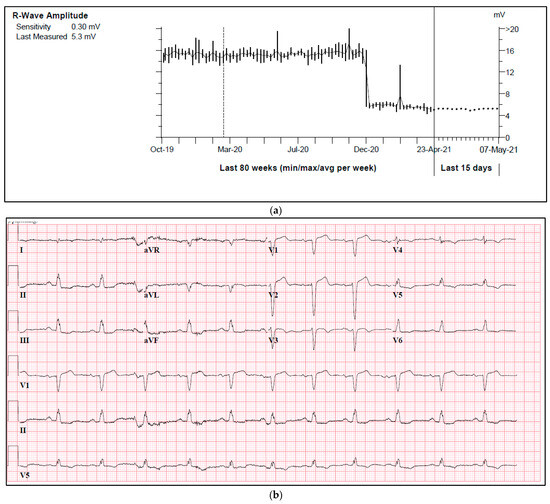

One of our cases was an adult patient with ischemic heart failure and a single lead ICD. During a routine check-up, a sudden drop in R-wave amplitude was observed in a true bipolar lead, with a reduction from 15 mV to 5 mV (Figure 2a). Both threshold and impedance remained stable. Further investigation revealed the presence of a new left anterior fascicular block on the ECG, which resulted in a change in the depolarization waveform and subsequently led to a decrease in R-wave amplitude (Figure 2b,c).

Figure 2.

(a) A sudden drop in R-wave amplitude caused by new onset left anterior fascicular block. (b) ECG prior to a drop in R-wave amplitude. (c) ECG after a drop in R-wave amplitude.